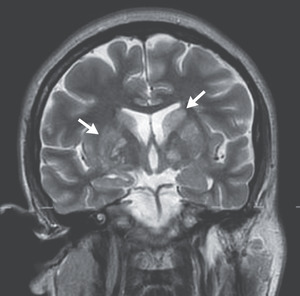

Covid-19 has been associated with a hypercoagulable state that can lead to pulmonary emboli, but this patient had a normal d-dimer level, a finding that makes pulmonary emboli unlikely. In addition, Covid-19 has been associated with encephalitis, but Covid-19 encephalitis usually occurs in the presence of severe pulmonary disease and is typically associated with frontotemporal hypoperfusion, leptomeningeal enhancement, or evidence of strokes on MRI.1,2 Venous sinus thrombosis can occur in patients with Covid-19, but there is no evidence of venous sinus thrombosis on MRI in this patient. I think Covid-19 is a coincidental diagnosis in this case and is not the most likely cause of the neurologic illness.

Given that this patient had recently immigrated to the United States, we need to consider possible diagnoses linked to Central America. Tuberculosis can cause meningitis with mononuclear pleocytosis, but with this infection, the CSF protein level is typically much higher than the level seen in this patient. In addition, he had no calcified granulomata on chest imaging; on brain imaging, we would be likely to see signs of meningitis or tuberculomas but not cystic-appearing lesions located in the basal ganglia. Cysticercosis is typically associated with either multiple, scattered enhancing cysts surrounded by edema in patients with active disease or calcifications of old cysts. Toxoplasmosis often involves the basal ganglia but typically causes ring-enhancing lesions with edema in immunocompromised patients. Chagas’ disease can cause meningoencephalitis and focal lesions during reactivation of infection in immunocompromised patients. Paracoccidioidomycosis is endemic in Central America, but neurologic involvement is uncommon and ring-enhancing lesions are usually seen. Coccidioidomycosis commonly causes meningitis, even in immunocompetent people, and although it is not endemic in Central America, we are not told how the patient traveled from Central America to Massachusetts; many immigrants undergo an arduous journey through the Sonoran Desert in northwestern Mexico. Both histoplasmosis and cryptococcosis can cause lymphocytic meningitis and are possible diagnoses in this case.7 Finally, because the patient did not have a fever and his inflammatory markers were not markedly abnormal, we need to consider noninfectious causes, specifically CNS lymphoma.

Cryptococcosis